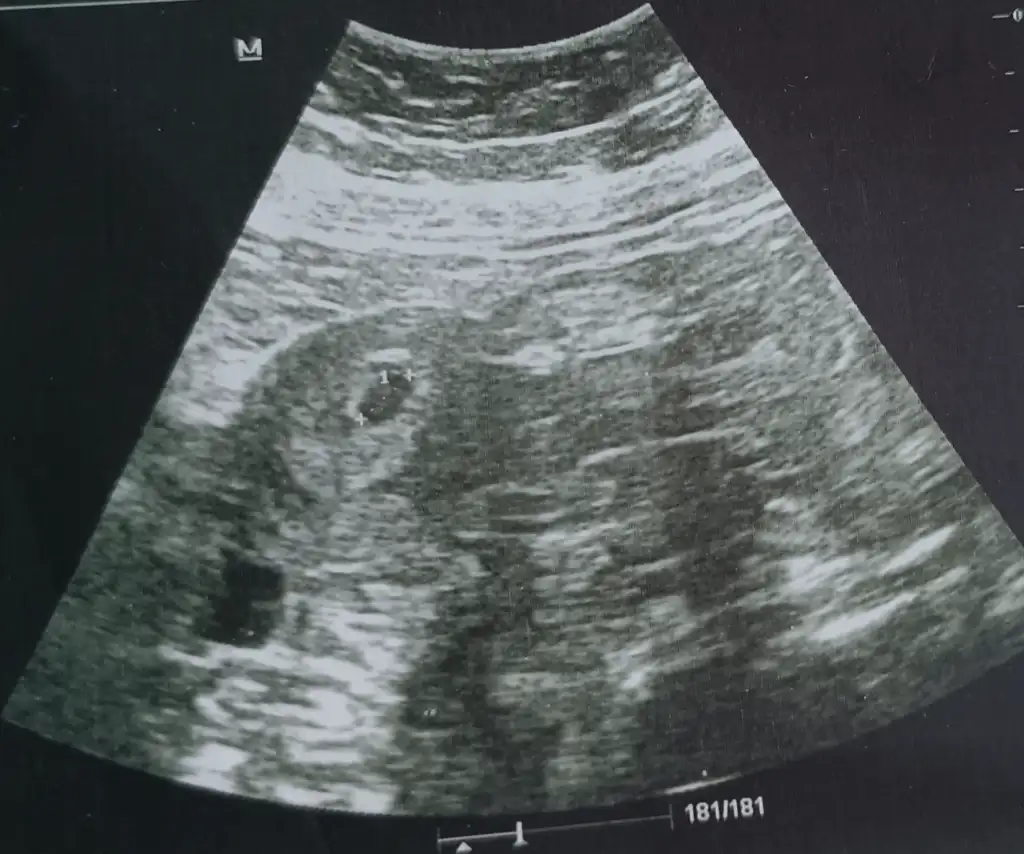

16 sinda 4+6 çıktı ultrasonda kese göründü, Bugün 6+0 oldu. Cuma gunu doktor randevum var 6+3 olacak kalp atışı duyulurmu bebek görünür mu sizce? Ultrasonu da ekliyorum 4+6 olan.